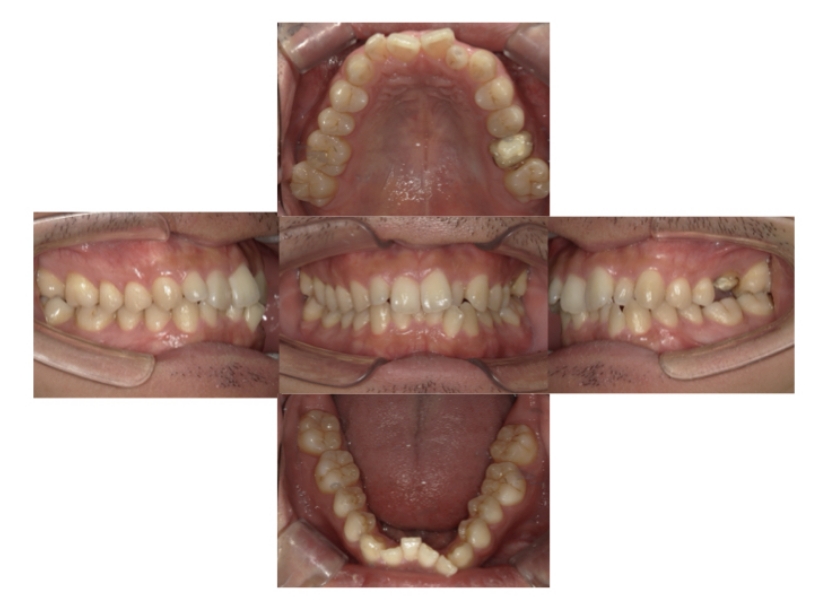

症例4

下顎前突、叢生

抜歯

ブラケット矯正

症例解説

上下顎叢生、反対咬合(上下の前歯のガタガタ、若干受け口)のケースです。

装置はラビアル(上下表側)で、上下顎の小臼歯を4本抜歯を行っています。抜歯したスペースを使って、上下の叢生改善と前歯の受け口の改善を行っています。

主訴 前歯のガタガタを治したい。

年齢・性別 45歳 女性

お住まいの地域 神奈川県川崎市

治療方針 抜歯スペースを利用して上前歯の叢生(ガタガタ)の改善と受け口の改善

抜歯部位 上顎左右第一小臼歯、下顎左右第二小臼歯

使用装置 ラビアル(上下表側)、顎間ゴム

治療期間 2年6か月

治療回数 20回

リテーナー クリアリテーナー

BEFORE

AFTER